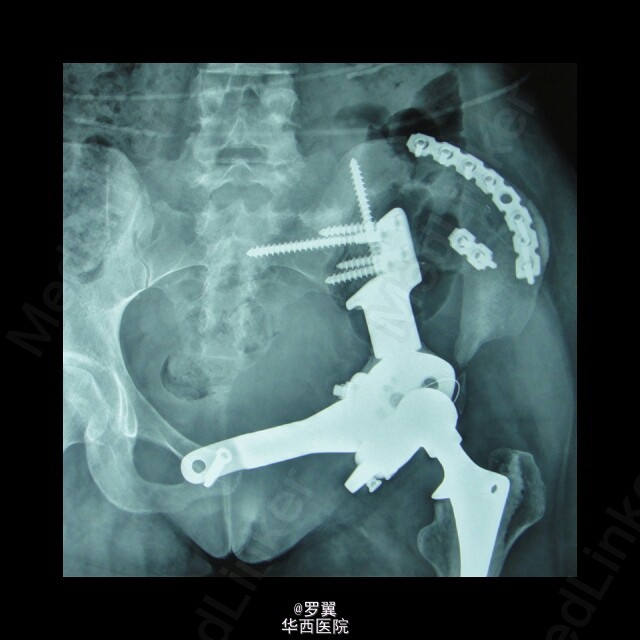

骨盆恶性肿瘤半骨盆假体置换术后髂骨断裂

患者23岁女性,骨盆恶性肿瘤半骨盆假体置换术后,进行髂骨保留并予钢板螺钉内固定,术后2年残留髂骨疲劳断裂。。